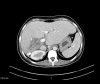

BACKGROUND Hydatid disease is a common parasitic infection in many areas of Asia, South America, and Africa. It can affect any organ, most commonly the liver. The hydatid is often asymptomatic and the diagnosis is made when complications arise. The most common complication of this disease is opening in the bile ducts, which is a life-threatening condition causing serious acute cholangitis. We report a case of acute cholangitis caused by hydatid cyst rupture into the right bile duct. CASE REPORT A 33-year-old woman, with no medical or surgical history, presented to our Emergency Department with abdominal pain, jaundice, and fever for 3 days prior to admission. The patient was hemodynamically stable. In the examination, we noticed right upper-quadrant tenderness with guarding, icterus sclera, and negative Murphy sign. A CT scan showed a liver hydatid cyst of the 4th and 8th of segments, with intrahepatic and extrahepatic biliary duct dilation. The cyst communicated with the right hepatic bile duct via a large fistula. A diagnosis of acute cholangitis was made and she underwent conservative treatment with external drainage of the pericystic cavity through the biliary duct. The postoperative course was uncomplicated and she was discharged 15 days later. CONCLUSIONS The surgical approach to hepatic hydatid must be customized based on the specific characteristics of the cyst and associated complications. Acute hydatid cholangitis is a rare but serious complication of a hydatid cyst, which requires early diagnosis and adequate surgical management.